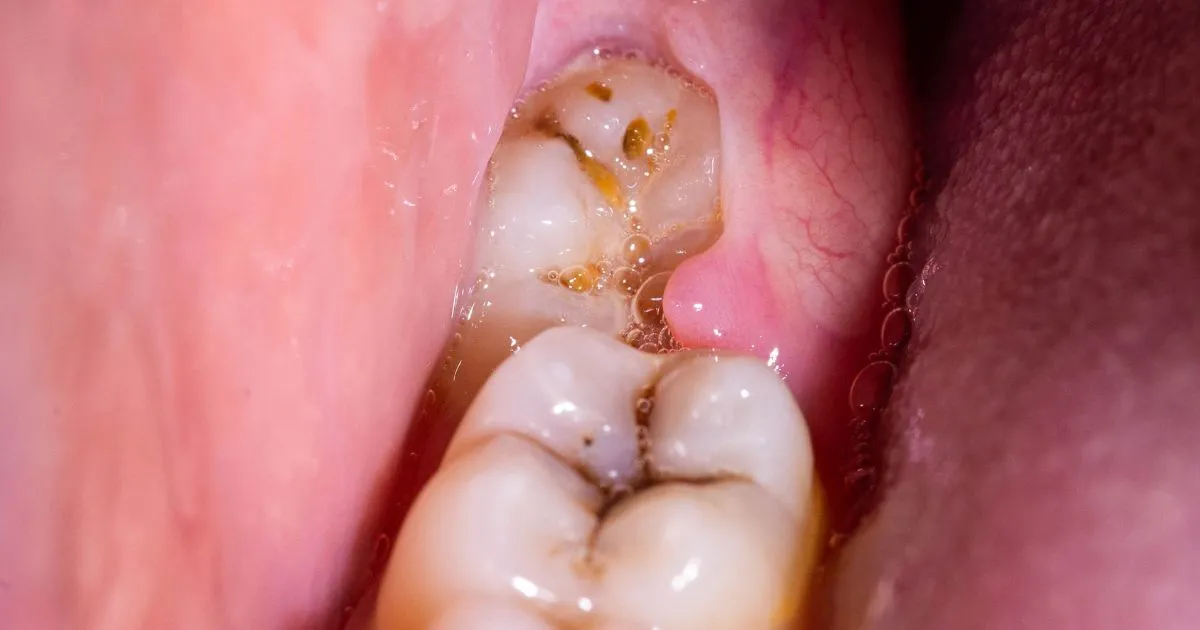

- Разрушение эмали, структуры. Воспаление десны – не единственное последствие недостаточной гигиены. Кариес – первое, что будет, если не удалять зуб мудрости. Из-за труднодоступного расположения лечение «восьмерки» проводится нечасто. Удаление – единственное правильное решение.